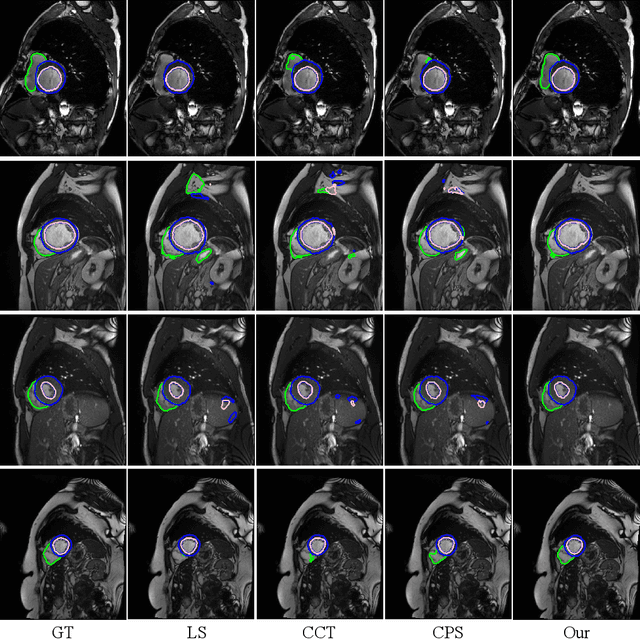

Abstract:Medical image segmentation plays an irreplaceable role in computer-assisted diagnosis, treatment planning, and following-up. Collecting and annotating a large-scale dataset is crucial to training a powerful segmentation model, but producing high-quality segmentation masks is an expensive and time-consuming procedure. Recently, weakly-supervised learning that uses sparse annotations (points, scribbles, bounding boxes) for network training has achieved encouraging performance and shown the potential for annotation cost reduction. However, due to the limited supervision signal of sparse annotations, it is still challenging to employ them for networks training directly. In this work, we propose a simple yet efficient scribble-supervised image segmentation method and apply it to cardiac MRI segmentation. Specifically, we employ a dual-branch network with one encoder and two slightly different decoders for image segmentation and dynamically mix the two decoders' predictions to generate pseudo labels for auxiliary supervision. By combining the scribble supervision and auxiliary pseudo labels supervision, the dual-branch network can efficiently learn from scribble annotations end-to-end. Experiments on the public ACDC dataset show that our method performs better than current scribble-supervised segmentation methods and also outperforms several semi-supervised segmentation methods.